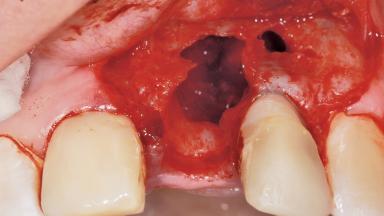

Late Placement of an Implant in a Maxillary Left Central Incisor Site

A 36-year-old female patient was referred for the replacement of the upper left central incisor (tooth 21), which had fractured. Although the tooth had been asymptomatic for many years, the crown began to loosen, at which time she presented to her dentist for an assessment. Teeth 21 and 22 had both been endodontically treated many years previously. She was a healthy individual and a non-smoker.

Bone Augmentation Horizontal|Staged

Bone Volume Deficient horizontally, requiring prior grafting